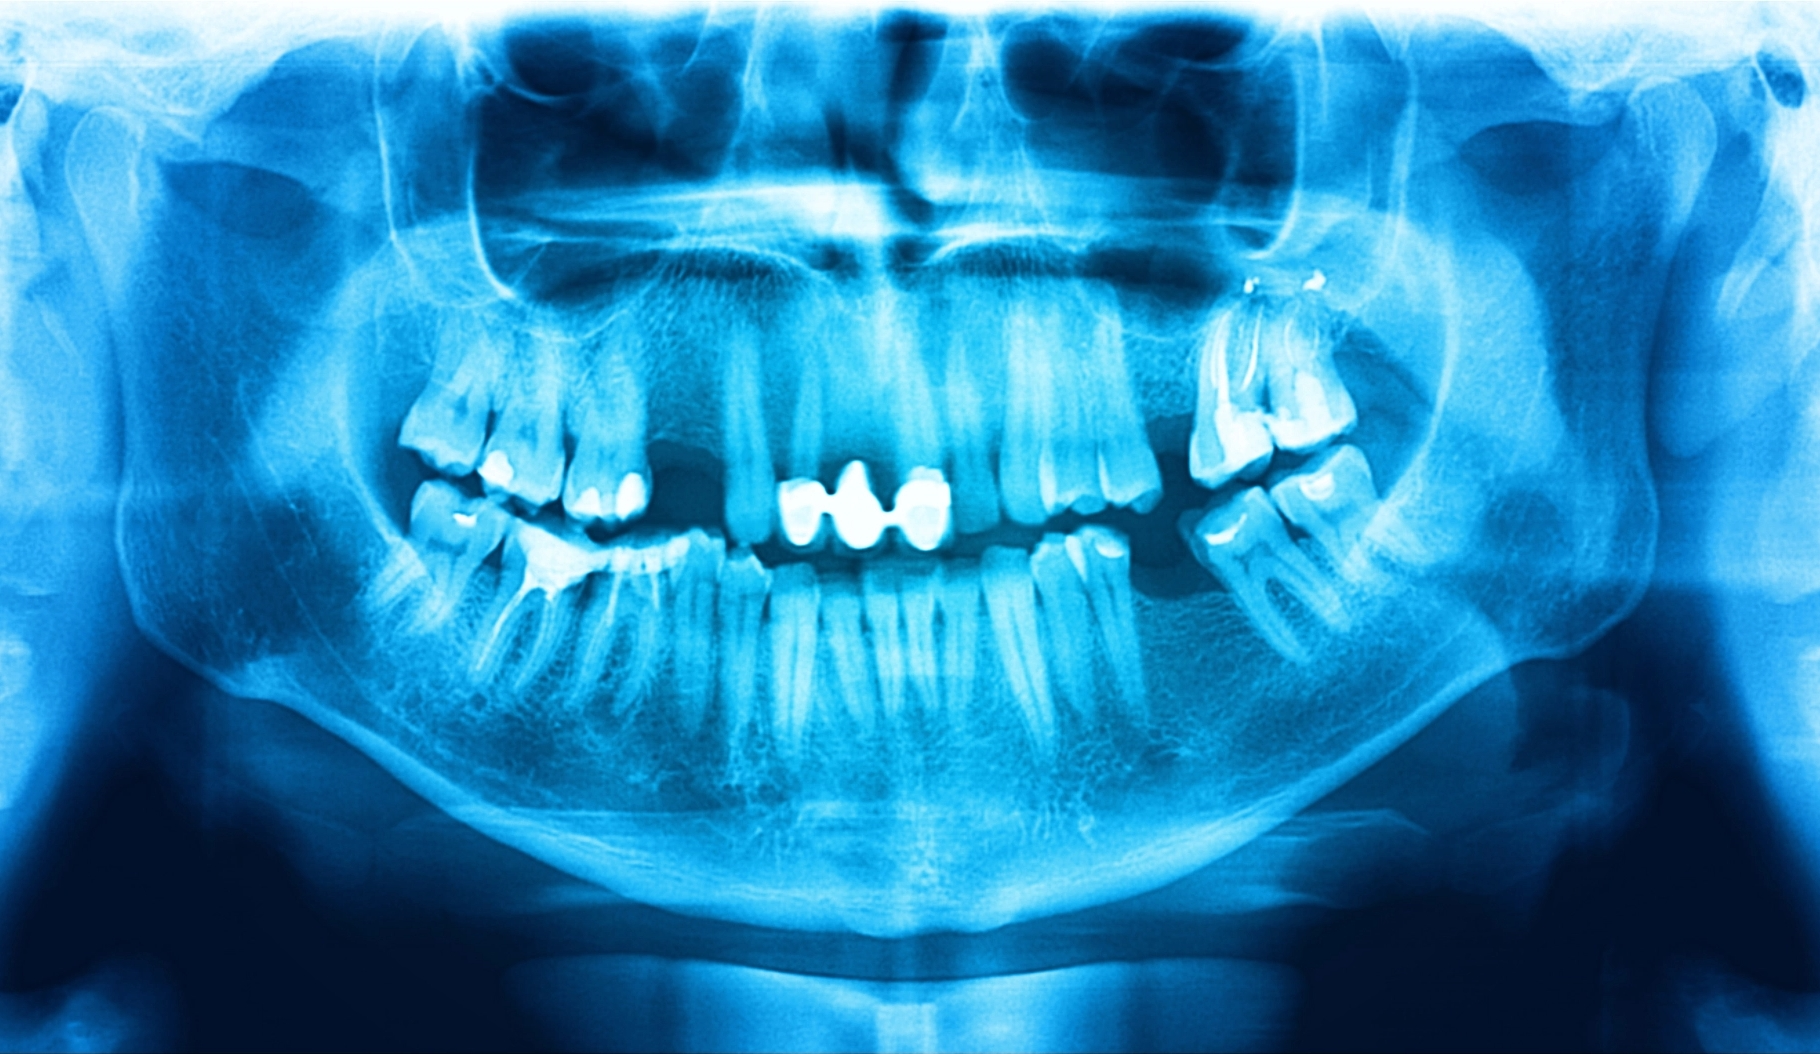

Cone Beam Imaging

Cone beam CT digital imaging technology is like a three-dimensional X-ray that is far more accurate than traditional X-rays, takes much less time, and does all this with much less radiation exposure. The dentist’s ability to clearly see the patient’s anatomy in 3-D leads to much greater accuracy for all dental treatment, especially implant placement and any oral surgeries.

Digital X-Rays

Traditional dental X-rays have been “good enough,” but digital X-rays provide clearer and much more accurate pictures of what’s going on inside a patient’s mouth. This makes it easier for the doctor to diagnose issues. Leaks or breaks in fillings that used to go unnoticed, often leading to root canals, can now be found and treated before major damage is done. We can also view your entire mouth in one shot, including the upper and lower jaws, with panoramic digital images.